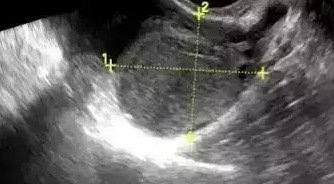

一个差点被误诊为卵巢早衰的病例

前北京协和医院妇产科副教龚晓明医生 这个上海的患者35岁,因为闭经3个月,在某大医院做了下性激素检测,结果出来FSH 50 IU/L(左侧报告单),直接被诊断为“卵巢早衰”,并告知患者生育无望,让她终生用芬吗通替代。电话咨询我,我看她超声子宫内膜有8mm,建议她用黄体酮撤退以后在月经第2-3天复查性激素,结果再次检查FSH为4.4 IU/L,这说明卵巢功能良好,生育还是非常有可能的。 为何之前被误